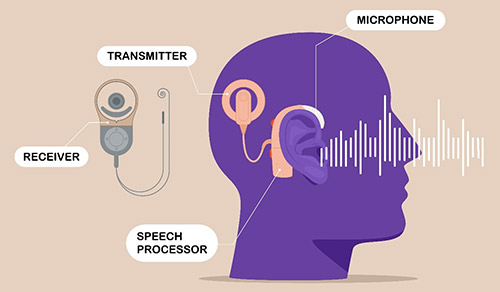

From novel minimally invasive approaches in head and neck surgery for benign and malignant tumors to programs dedicated to voice preservation and recovery, restoring hearing, and managing sleep disorders, our otolaryngologists and laryngologists from Columbia and Weill Cornell Medicine offer patients diagnostic and therapeutic procedures that optimize functional and aesthetic outcomes.